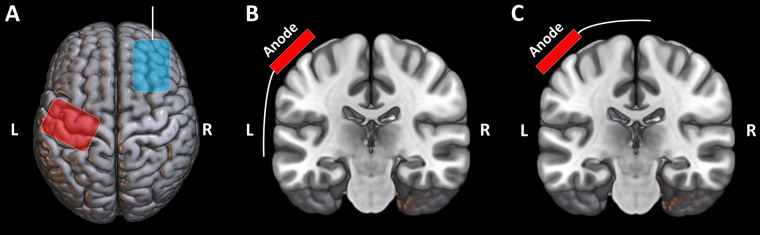

Methods: In this single-blinded, randomized, sham-controlled study, 53 healthy volunteers were assigned to one of 4 groups, receiving either real tDCS or sham tDCS, with the anodal connector oriented either superior-medially or ventral-laterally. tDCS was delivered on 5 consecutive days with the anode and cathode placed over the left primary sensorimotor cortex (SM1) and the right dorsolateral prefrontal cortex, respectively. Pain detection thresholds (PT) and moderate pain thresholds (MPT) of the right index finger and GABA levels from the bilateral SM1 were obtained prior to tDCS, after 5 tDCS sessions, and after 6 weeks.